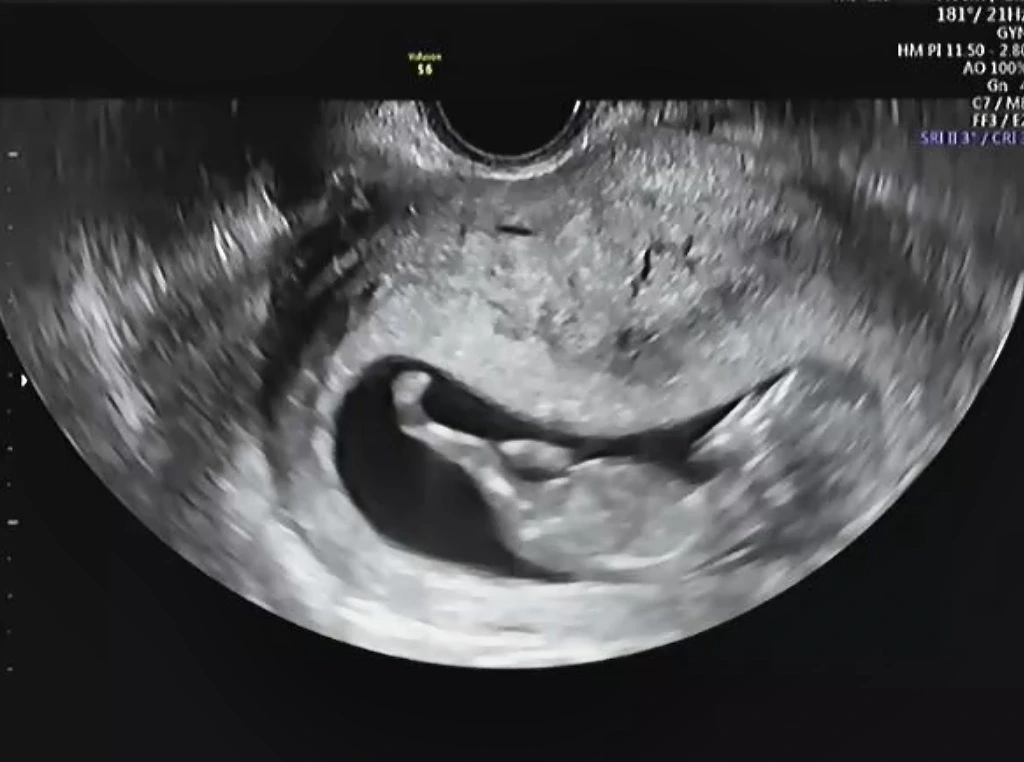

그리고 얼마 지나지 않아, 우리에게도 아기 천사가 찾아왔다.

2021년 4월에 태어날 꼬마가 봄의 좋은 기운을 가득 담길 바라는 마음에 봄봄이라는 태명을 지어주었다. 모두가 간절히 기다렸는지, 우리가 생각했던 것보다 거듭 진한 축하를 받았다. 나의 기쁨을 축하하는 지인의 눈물이 이토록 감사하고 벅찬 기분인지 처음으로 느껴보았다. 기쁨은 정말 나누면 배가 되는 건가 보다. 우리 만큼의 기쁨을 함께해줄 가족과 지인이 있음에 감사했다. 더불어 우리 인간에게는 감정을 함께 나눌 사람이 꼭 필요하다는 것을 다시 한번 깨달았다.